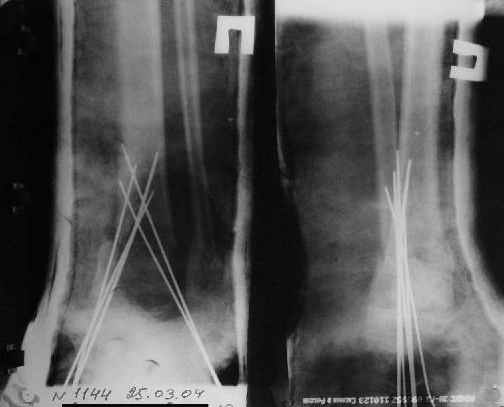

Первичные

|